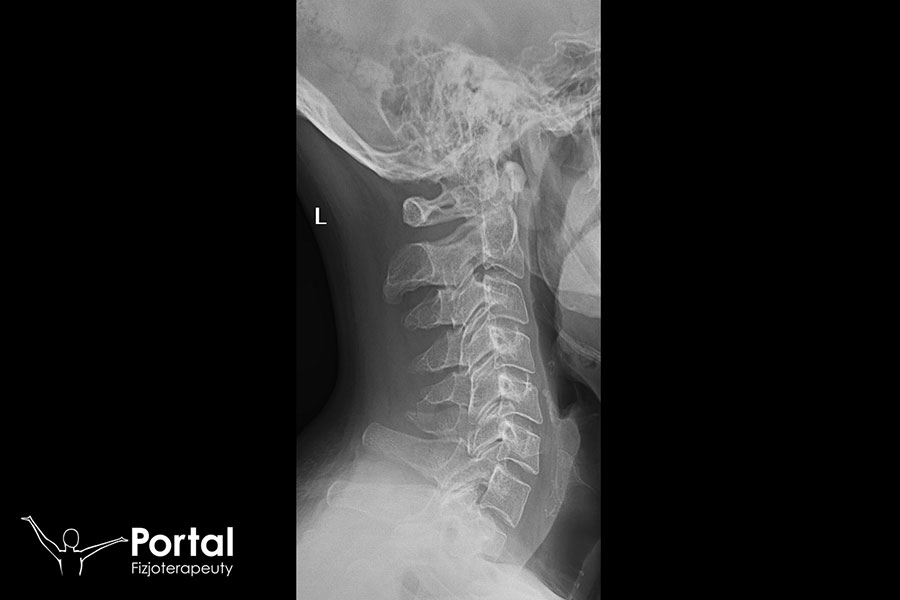

Przewlekłe bóle w kręgosłupie wymagają wykonania badań obrazowych, wśród których największe znaczenie ma rezonans magnetyczny. Ukazuje on zarówno kręgi i struktury kostne, jak i stawy, więzadła, kanał kręgowy czy krążki międzykręgowe. Z najwyższą precyzją pozwalają zdiagnozować m.in. dyskopatię, co nie jest możliwe na podstawie badania RTG. Jednocześnie warto udać się do fizjoterapeuty, który oceni napięcie mięśni i obecność na ich przebiegu tzw. punktów spustowych, które mogą generować ból kręgosłupa. Ważna jest też analiza postawy ciała i wykrycie ewentualnych wad postawy.